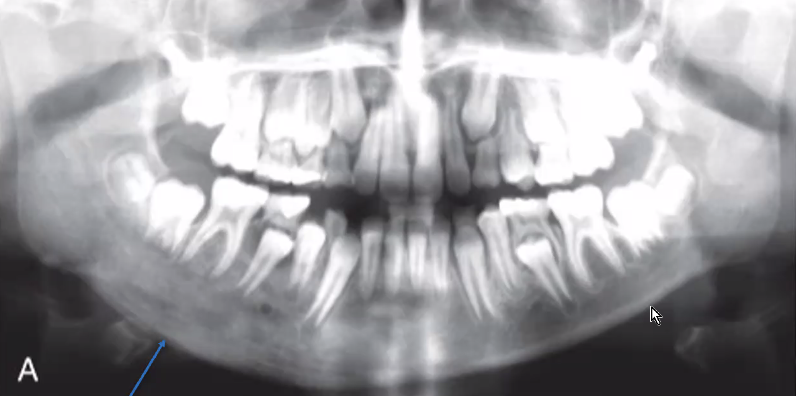

osteomyelitis

infection invades bone

body tries to โwall offโ dental infection

if body does not succeed, osteomyelitis can occur

mixed radiolucencies/radiopacities in irregular manner